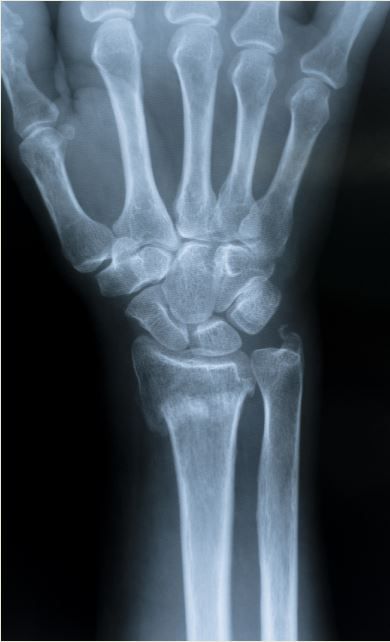

Example of distal radial epiphysis fracture

Fractures of the distal aspect of the radius are common, yet little is known about this type of fracture among older men. Distal radial fracture is the most common upper extremity fracture and is associated with increased risk of future fractures. Recent data show that patients experience peak rates of distal radial fracture between ages 50 and 64.